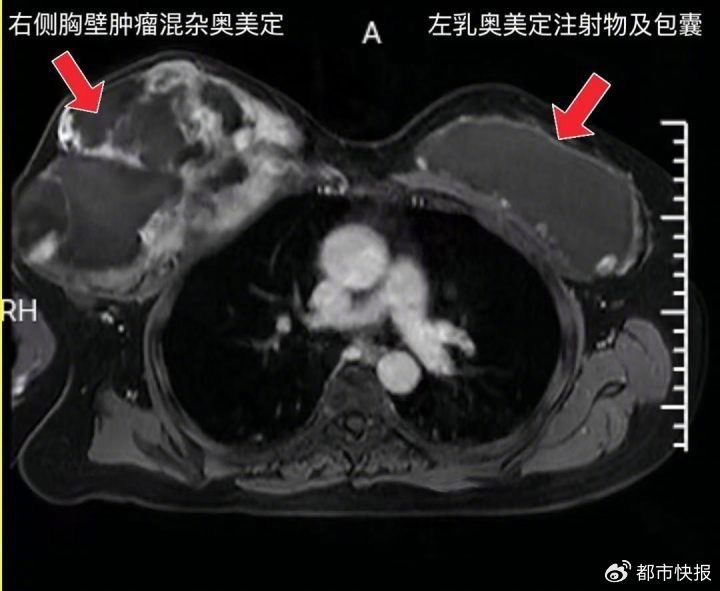

陈女士20年前收受了双乳奥好意思定隆胸,跟着时间推移,奥好意思定刺激右侧胸壁酿成了一个庞杂的肿块,足足有约25×30厘米大小!经过穿刺确诊,这个肿块竟是梭形细胞赘瘤——一种高度恶性的软组织肿瘤。由于肿瘤已扰乱胸壁深层组织,周济春医师团队不得不报复进行手术切除肿瘤,并取出双侧乳房内的奥好意思定凝胶。

术中发现,奥好意思定已凡俗侵袭双侧胸大肌和乳房组织,囊壁内充满了淡黄色、半糊状的流质物资,局部甚而呈鹅卵石样改造。那就意味着,若是再拖延不取出打针物及包囊,左侧胸壁恭候陈女士的也将是可怕的癌症。